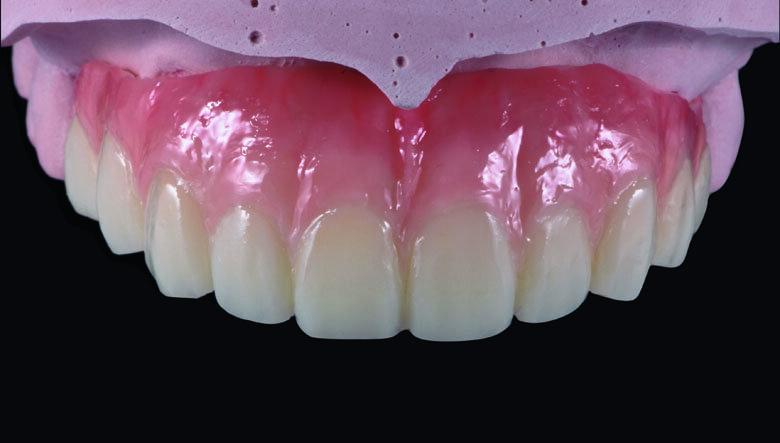

Fig 19. Completed Provisional Profile Prosthesis with gingival aesthetics that mimic nature

Preparation cast with a diagnostic wax-up ca st was sent to a local laboratory for scanning and transforming into STL (Stereolithography) digital impression file. (Fig 8,9.) Two sets of STL impressions were super-imposed in the software in order to subtract the overlapping data. This process was done in order to transform the diagnostic wax-up into the STL digital impression. Consequently, the STL data was sent to the laboratory for milling. (Fig10.) A monochromatic milled-PMMA temporary bridge was fabricated in a local laboratory and returned to the dentist for composite layering. (Fig 11.) Gingival cutback was made to create sufficient gingival space for pink composite layering (Fig 12). Prior to composite layering CeraResin Bond 1 was applied and left for 10 seconds to prime the surface, followed by application of CeraResin Bond 2 for 10 seconds and light cured for 20 seconds (Fig 13.). Ceramage Indirect Composite gingival shade GUM-O (GUM Opaque) was applied to mask the color of PMMA (Fig 14.). GUM-D (GUM Dark) was applied on the attached gingiva area to the buccal flange (Fig 15.). GUM-L (GUM Light) was applied in the region of free gingiva (Fig 16.). F-GUM-R (Flowable GUM Red) and F-W (Flowable GUM White) were painted to mimic the mucogingival junction and vascular alveolar mucosa (Fig 17.) GUM-T (GUM Translucent) was applied to reproduce of reddish translucent gingiva areas (Fig 18) to achieve natural gingival aesthetics.

Contouring, Finishing and Polishing of temporary restoration

Meticulous finishing and polishing of the restoration is a crucial step to achieving the desired aesthetics. Dura-Green stone was used to contour the macro anatomical details while the Robot Carbide Fissure Bur was used to shape the interproximal and papilla areas. The course silicone points followed by Dura-Polishing paste Al2O3 with a medium strong brush was used to finish and pre-polish the restoration. Dura-Polish DIA, diamond polishing paste was applied with a fine brush followed by the cotton buff to achieve the final high-luster polishing (Fig 19.)1.